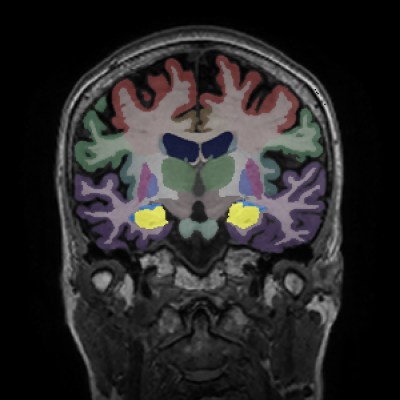

Alzheimer's Disease Case Study 1

Retrospective brain volumetric analysis in a female patient diagnosed with Alzheimer’s disease at age 77 showed progressive brain atrophy over a 5-year period. The scans demonstrate both hippocampal volume loss and a clear left–right asymmetry.

PATIENT

Female patient diagnosed with Alzheimer's Disease at Age 77

Analysis period

5 years

regions of interest

Hippocampi

Inferior lateral ventricles

Age 72

Age 76

Age 77

Whole brain